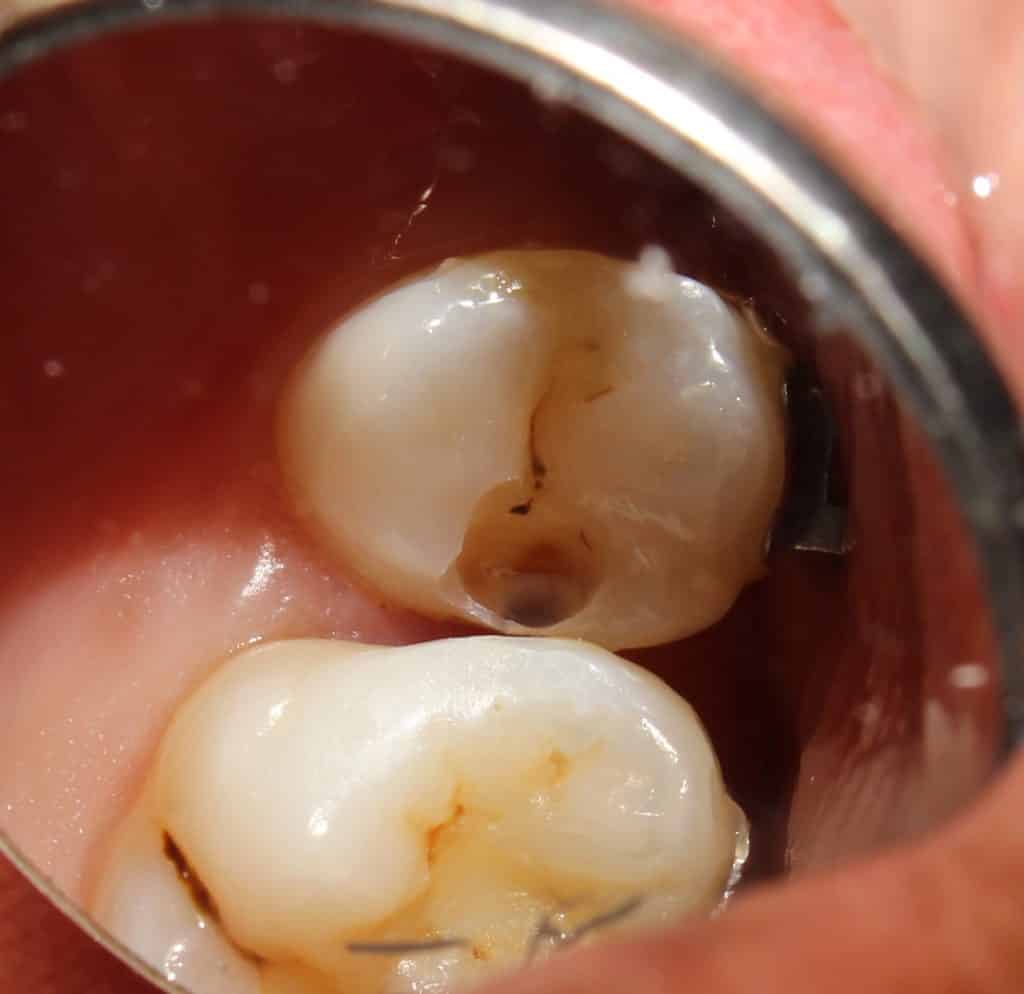

initial entry into 15 showing the proximal caries..

on entry.. the caries on the mesial of the molar is seen..

as caries removal is started.. the extent of the decay is noted..